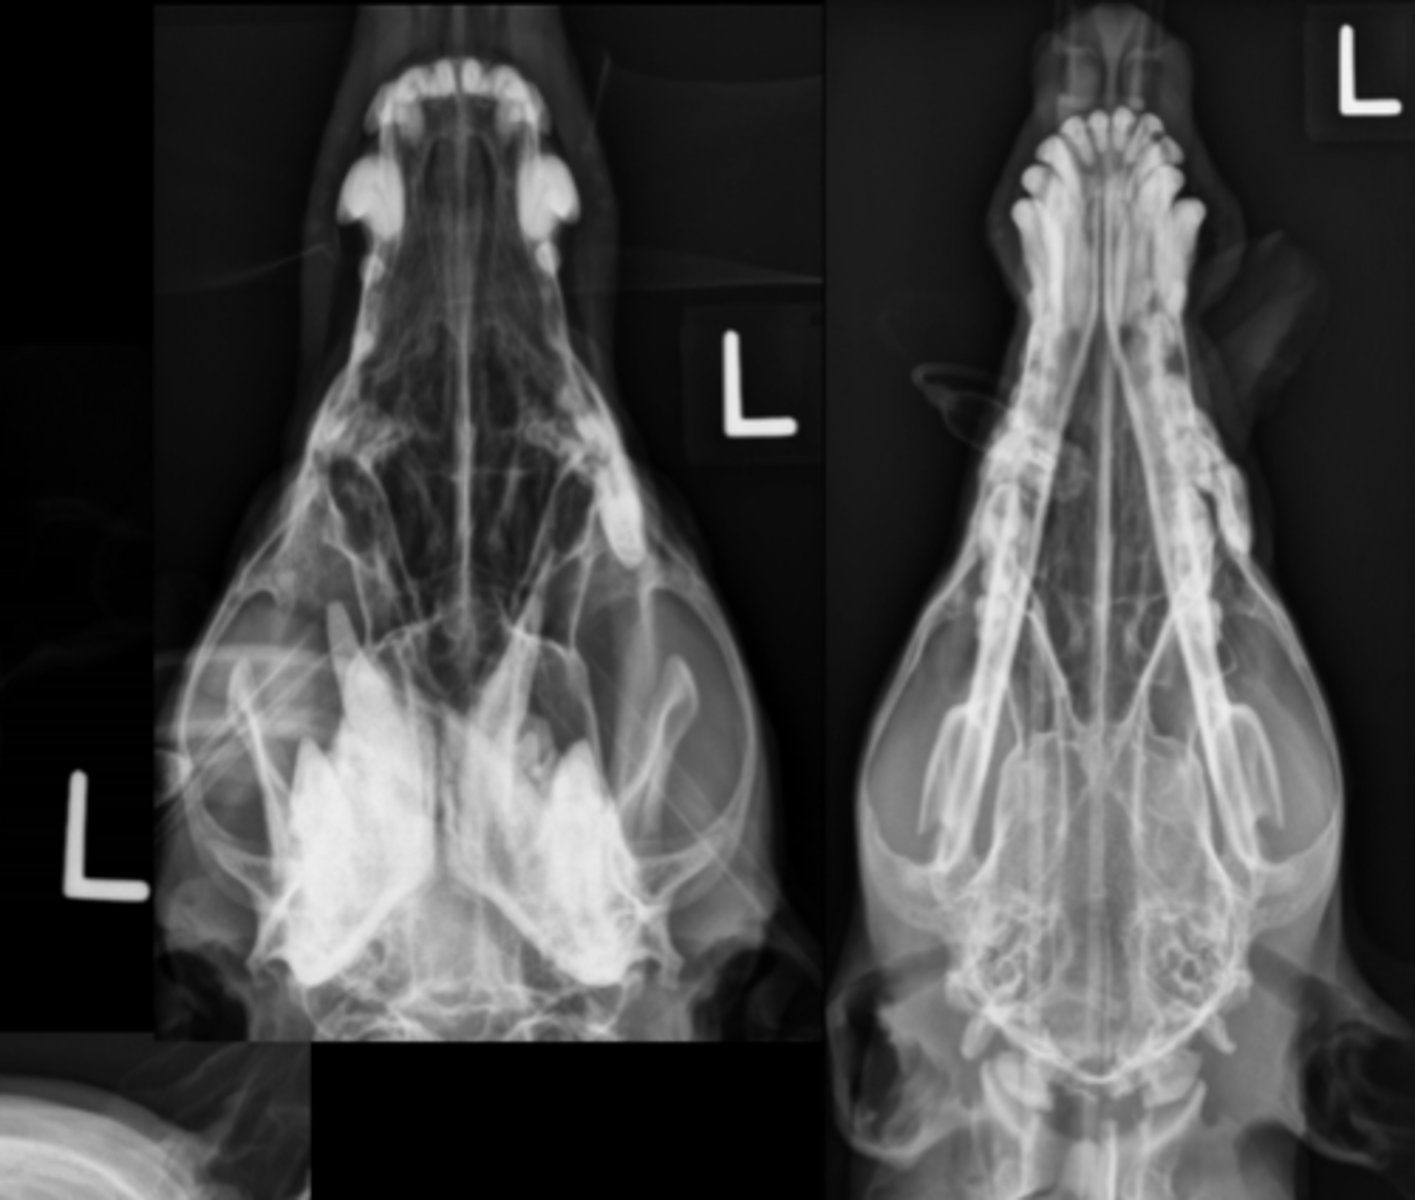

Canine Skull